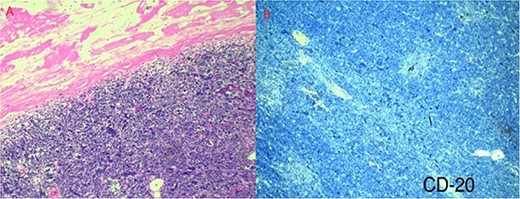

Pathology reported a 38 × 29 × 28 mm smooth tumor. It had a grayish external surface, few cystic areas and yellowish serous contents. The microscopic report revealed a well-defined tumor, surrounded by a thickened fibrous connective capsule with focal areas of calcification without invasion and numerous small CD5-positive lymphocytes (Fig. 3). B2 Thymoma in the mediastinum was the final diagnosis.

(a) Well-defined tumor formation, surrounded by a thickened fibrous connective capsule with focal areas of calcification and numerous small CD5-positive lymphocytes. (b) Immunohistochemistry shows a proliferative index of 30% with isolated positivity for CD20-positive B lymphocytes.